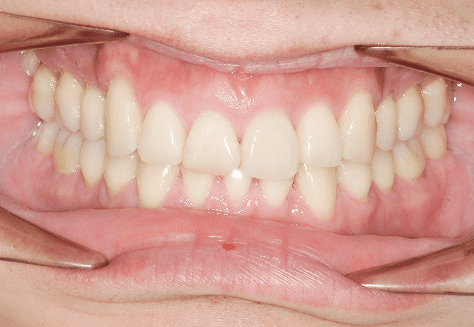

S.K

治療前

治療後

主訴

歯が重なっていて気になる。前歯が出ていて唇が閉じにくい。ハミガキがしにくい。

診断

上顎前突・叢生

年齢/性別

20代/男性

抜歯部位

上下第三大臼歯

使用装置

上下インビザライン

保定装置

上下ビベラリテーナー

料金

初回資料採得・・・・・・・30,000円

診断料・・・・・・・・・・33,000円

動的治療終了時資料採得・・5,500円 -

基本料金

990,000円

診察料金

1,100円×33回

-

治療期間

3年5カ月